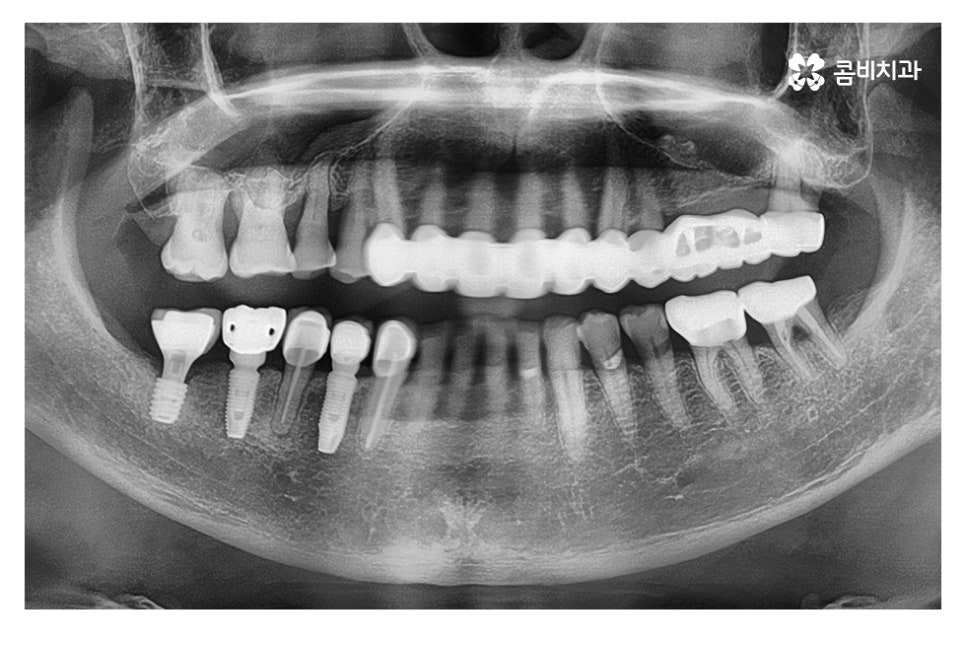

위 케이스의 경우 영구치가 손실된 상태에서 시간이

어느 정도 경과된 후 임플란트 수술을 진행하였으며,

영구치가 손실되고 어느 정도 뼈가 차있고, 현 상태에서

식립이 가능했기 때문에 뼈이식 없이 임플란트를 식립하였고

이때 골 유착 과정을 거치면서 임플란트가 단단하게 고정되고

치료가 마무리되면 자연치아에 버금가는 저작력을 갖추게 될 수 있어요.